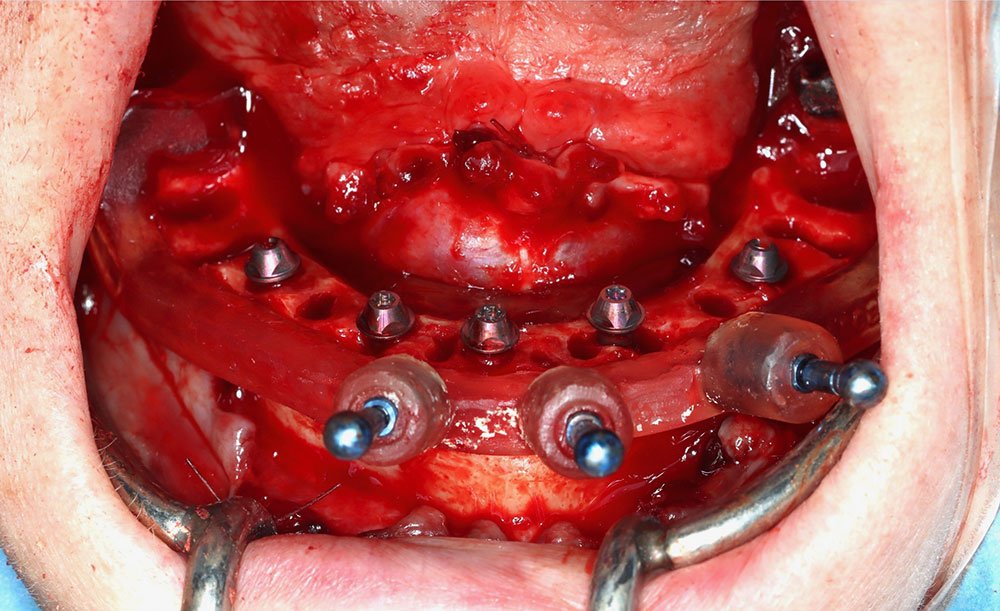

- LIVE surgery demonstration

The aim of this live surgery course is to look deeply and carefully at the procedures, skills, and techniques required to provide excellent predictable aesthetic dental implant surgery. In this residency, delegates will have the opportunity to dig further into the techniques and skills required to provide excellent implant surgery, watching and performing their own live surgeries! Various techniques will be investigated, including discussions around modern techniques such as immediate implant dentistry, grafting techniques, live surgery performed by Dr. Dagher, guided surgery protocols and guidance on how to position a collaborative approach with your team to present implant treatment options to more patients.

The Advanced Implant Residency will focus on 4 main topics: Grafting, Sinus lift, Immediate loading and Bone grafting. There will be ample room for full discussion related to all of the above together with the opportunity to review cases of your own patients with Dr. Dagher and perform them under his supervision on site. This ongoing residency will be offered yearly at the Dagher Institute for Advanced Learning. This will provide delegates with a much deeper understanding of aesthetic implant surgery including ongoing support and mentorship from Dr. Dagher. Straumann is proud to collaborate with Dr. Dagher in Hawkesbury to bring you the most comprehensive and advance learning institute in the area.

- Immediate loading protocols (partially and fully edentulous)